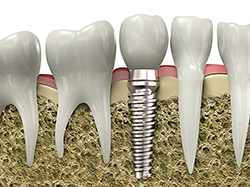

An implant is a synthetic tooth root in the shape of a post that is surgically placed into the jawbone. The “root” is usually made of titanium: the same material used in many replacement hips and knees, and a metal that is well-suited to pairing with human bone. A replacement tooth is then fixed to the post. The tooth can be either permanently attached or removable. Permanent teeth are more stable and feel more like natural teeth.

The “root” of a dental implant is a small, post-like device made from titanium or titanium zirconium. It is inserted into the jaw bone in place of a missing tooth root, and acts as a support for an artificial tooth crown.

The healing phase lasts between three and 12 weeks, depending on the individual medical situation. During this period, the implant becomes securely attached as the jaw bone grows and bonds with it—a process called osseointegration. Once healed, the artificial root acts as a base for an individual crown, multi-tooth bridge, or an entire dental prosthesis.